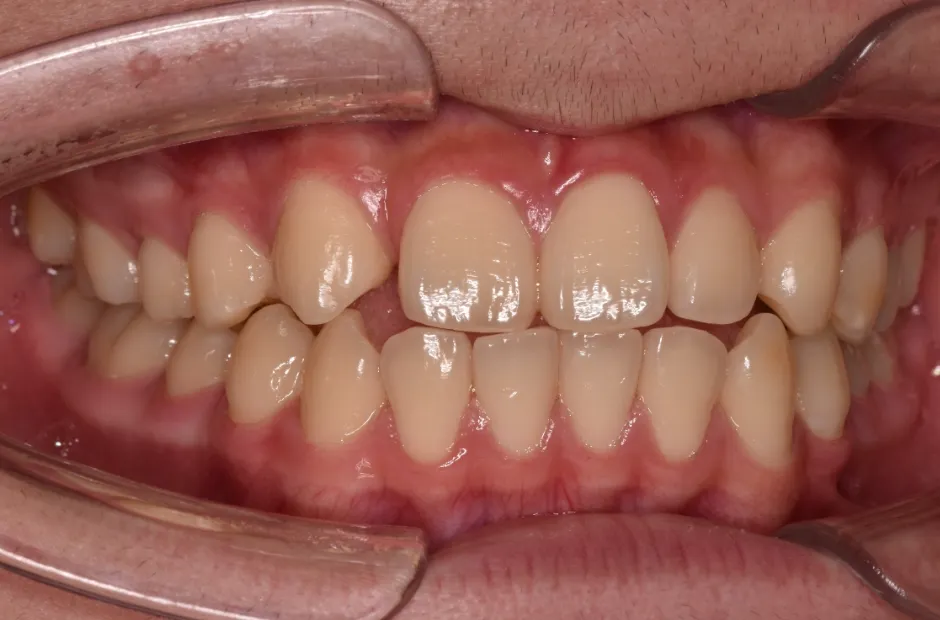

治療症例

ブラケット矯正

前歯部反対咬合

| 診断名・主訴 | 前歯部反対咬合 |

|---|---|

| 年齢・性別 | 14歳・男性 |

| 治療期間・回数 | 1年2か月 |

| 治療に用いた主な装置 | ブラケット矯正 |

| 抜歯部位 | なし |

| 治療費 | 60万円(税抜) |

| リスク・副作用 | 装置による違和感・疼痛・歯肉退縮・歯根吸収・虫歯のリスクなど |

治療前

治療後